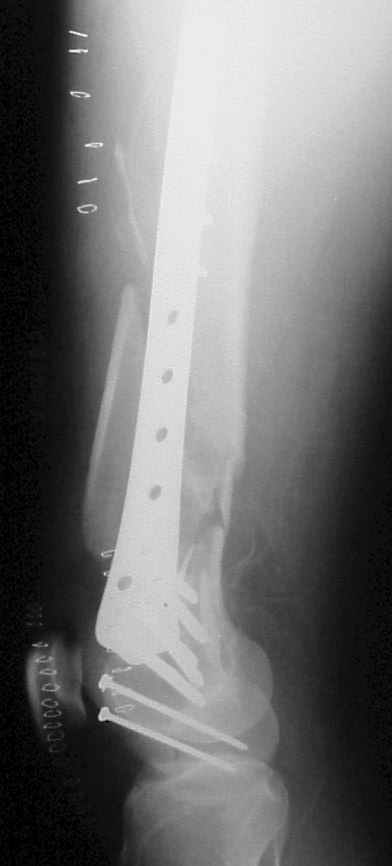

- Right femur fracture (33-C3.3) open grade III-A

On Wednesday we operated him, we used a LISS plate in either bone, when drillind we had the feeling of a 'normal' bone.

On Thersday afternoon he was alright, he is a very active man and he was moving well both knees. Later that evening he told me that while he was a little bit asleep he turned on the bed and felt pain and that the femur was loose. Here are the X-rays we took.

In this case, the fixation might have failed because of inadequate purchase of the side plate to the shaft. I say this because the initial lateral xray shows that the plate seems to be fairly anterior to the mid-axis of the femoral shaft. Once the plate pulled off of the shaft, it continued to pull out of the distal segment. With the short unicortical screws used for shaft fixation, it is imperative that the plate be applied precisely at the midline (widest diameter) of the femur. If it is applied even slightly anterior or posterior to the midline, the screws just don¹t engage the cortex. You can¹t tell by feel, since the screws lock firmly into the plate.

A second "pearl" is to place at least one or 2 lag screws between the condyles for intrafragmentary fixation before applying the LISS. Although screws were used across the coronal plane (Hoffa) fracture, I do not see any lag screws from lateral to medial. The LISS screws are designed to maintain the reduction of the distal femoral condylar mass to the shaft, but they do not function as lag screws. The intra-articular portion of the fracture demands open reduction and rigid internal fixation according to established

principles; the LISS is used to then stabilize the reconstructed distal femur to the shaft.

I was teached not to put the plate in the middle of the shaft in a true lateral view of the femur, but rather slight anterior and internally rotated so the end part will adapt to the trapezoid shape of condyles, but still the screws will be in the maximum diameter of the shaft. On the post-op X-ray you can see a true lateral view of the femur (the posterior part of the condyles are aligned) but not of the plate (you can see them coming under). I can assure you that the plate was completely centered on the shaft.

On intraoperative fluoroscopy with external rotation of the thight we confirmed that the plate was completely centered in that case.

Lateral x-ray does not adequately show proximal shaft & plate alignment with it. Do you think the plate was too anterior. This is an acknowledged mode of failure, as tangential unicortical screws may have minimal purchase, inspite of drill-tip passing through hard bone, and of course “good torque” as screw is tightened (into plate). If not easy to confirm intra-operatively, a short proximal incision can help to ensure correct alignment of plate with shaft.

Condyles have separated. Would separate (peripheral ? 3.5mm, lag screws, medial to lateral or lateral to medial outside LISS footprint) lag screws have been helpful? Intercondylar fracture needs open reduction and good interfragmentary compression.

LISS is a bit proximal, and screws are not parallel with joint line. Is there excessive valgus on appropriate AP views? You might want to check the mechanical axis using electrocautery cord stretched across knee, from center of femoral head to middle of talus.